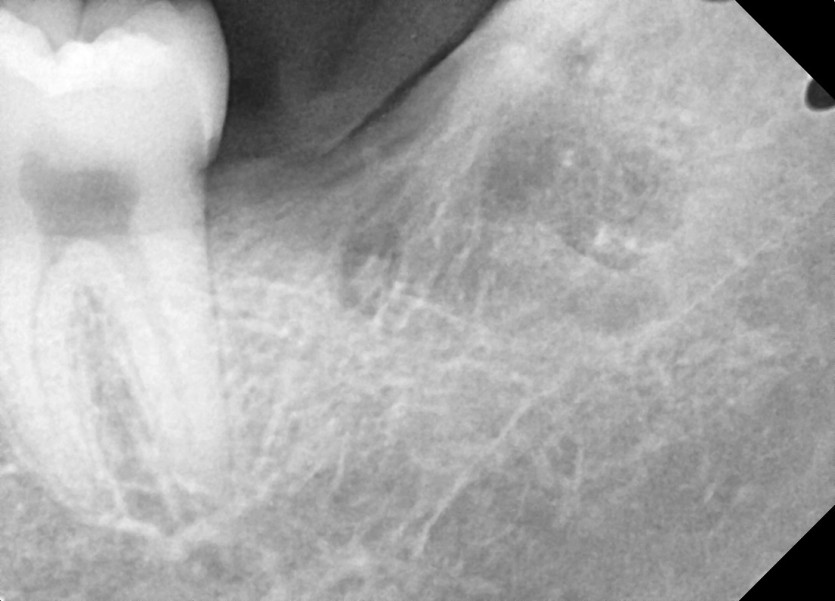

#28,38 사랑니 발치

구강 외과 전문의가 당일 발치했습니다.